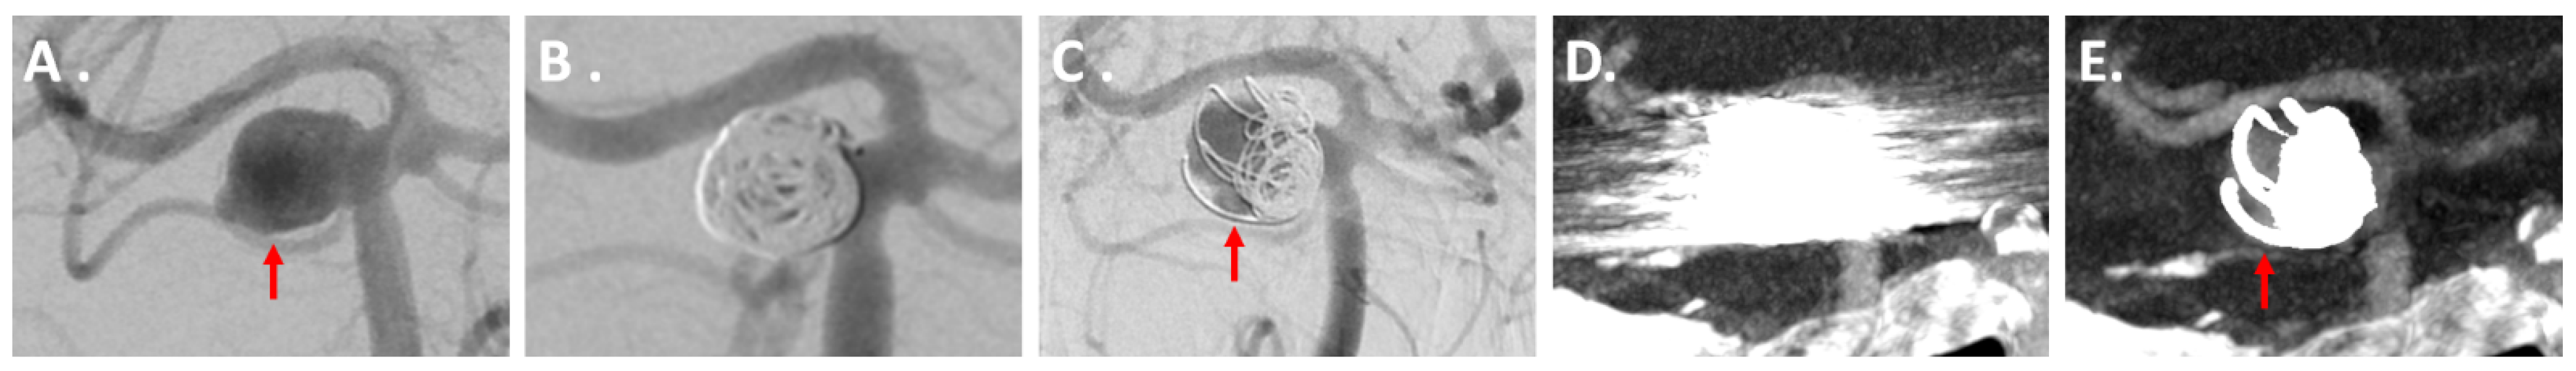

Figure 2, Figure 3 and Figure 4 show exemplary images of DSA data and the corresponding iMAR−/iMAR+ FD-CTA of both patients with IAs treated via endovascular coiling and intracranial clipping.

Figure 2. A 63-year-old patient with an aneurysm of the basilar artery in the initial DSA ((A) red arrow) with consecutive treatment via endovascular coiling (B). Six months later, DSA control revealed a reperfusion in the aneurysm center ((C) red arrow). The aneurysm was not assessable in iMAR− FD-CTA due to severe metal artifacts (D). After application of iMAR and the following significant metal artifact reduction, FD-CTA also demonstrated reperfusion in the aneurysm center ((E) red arrow).